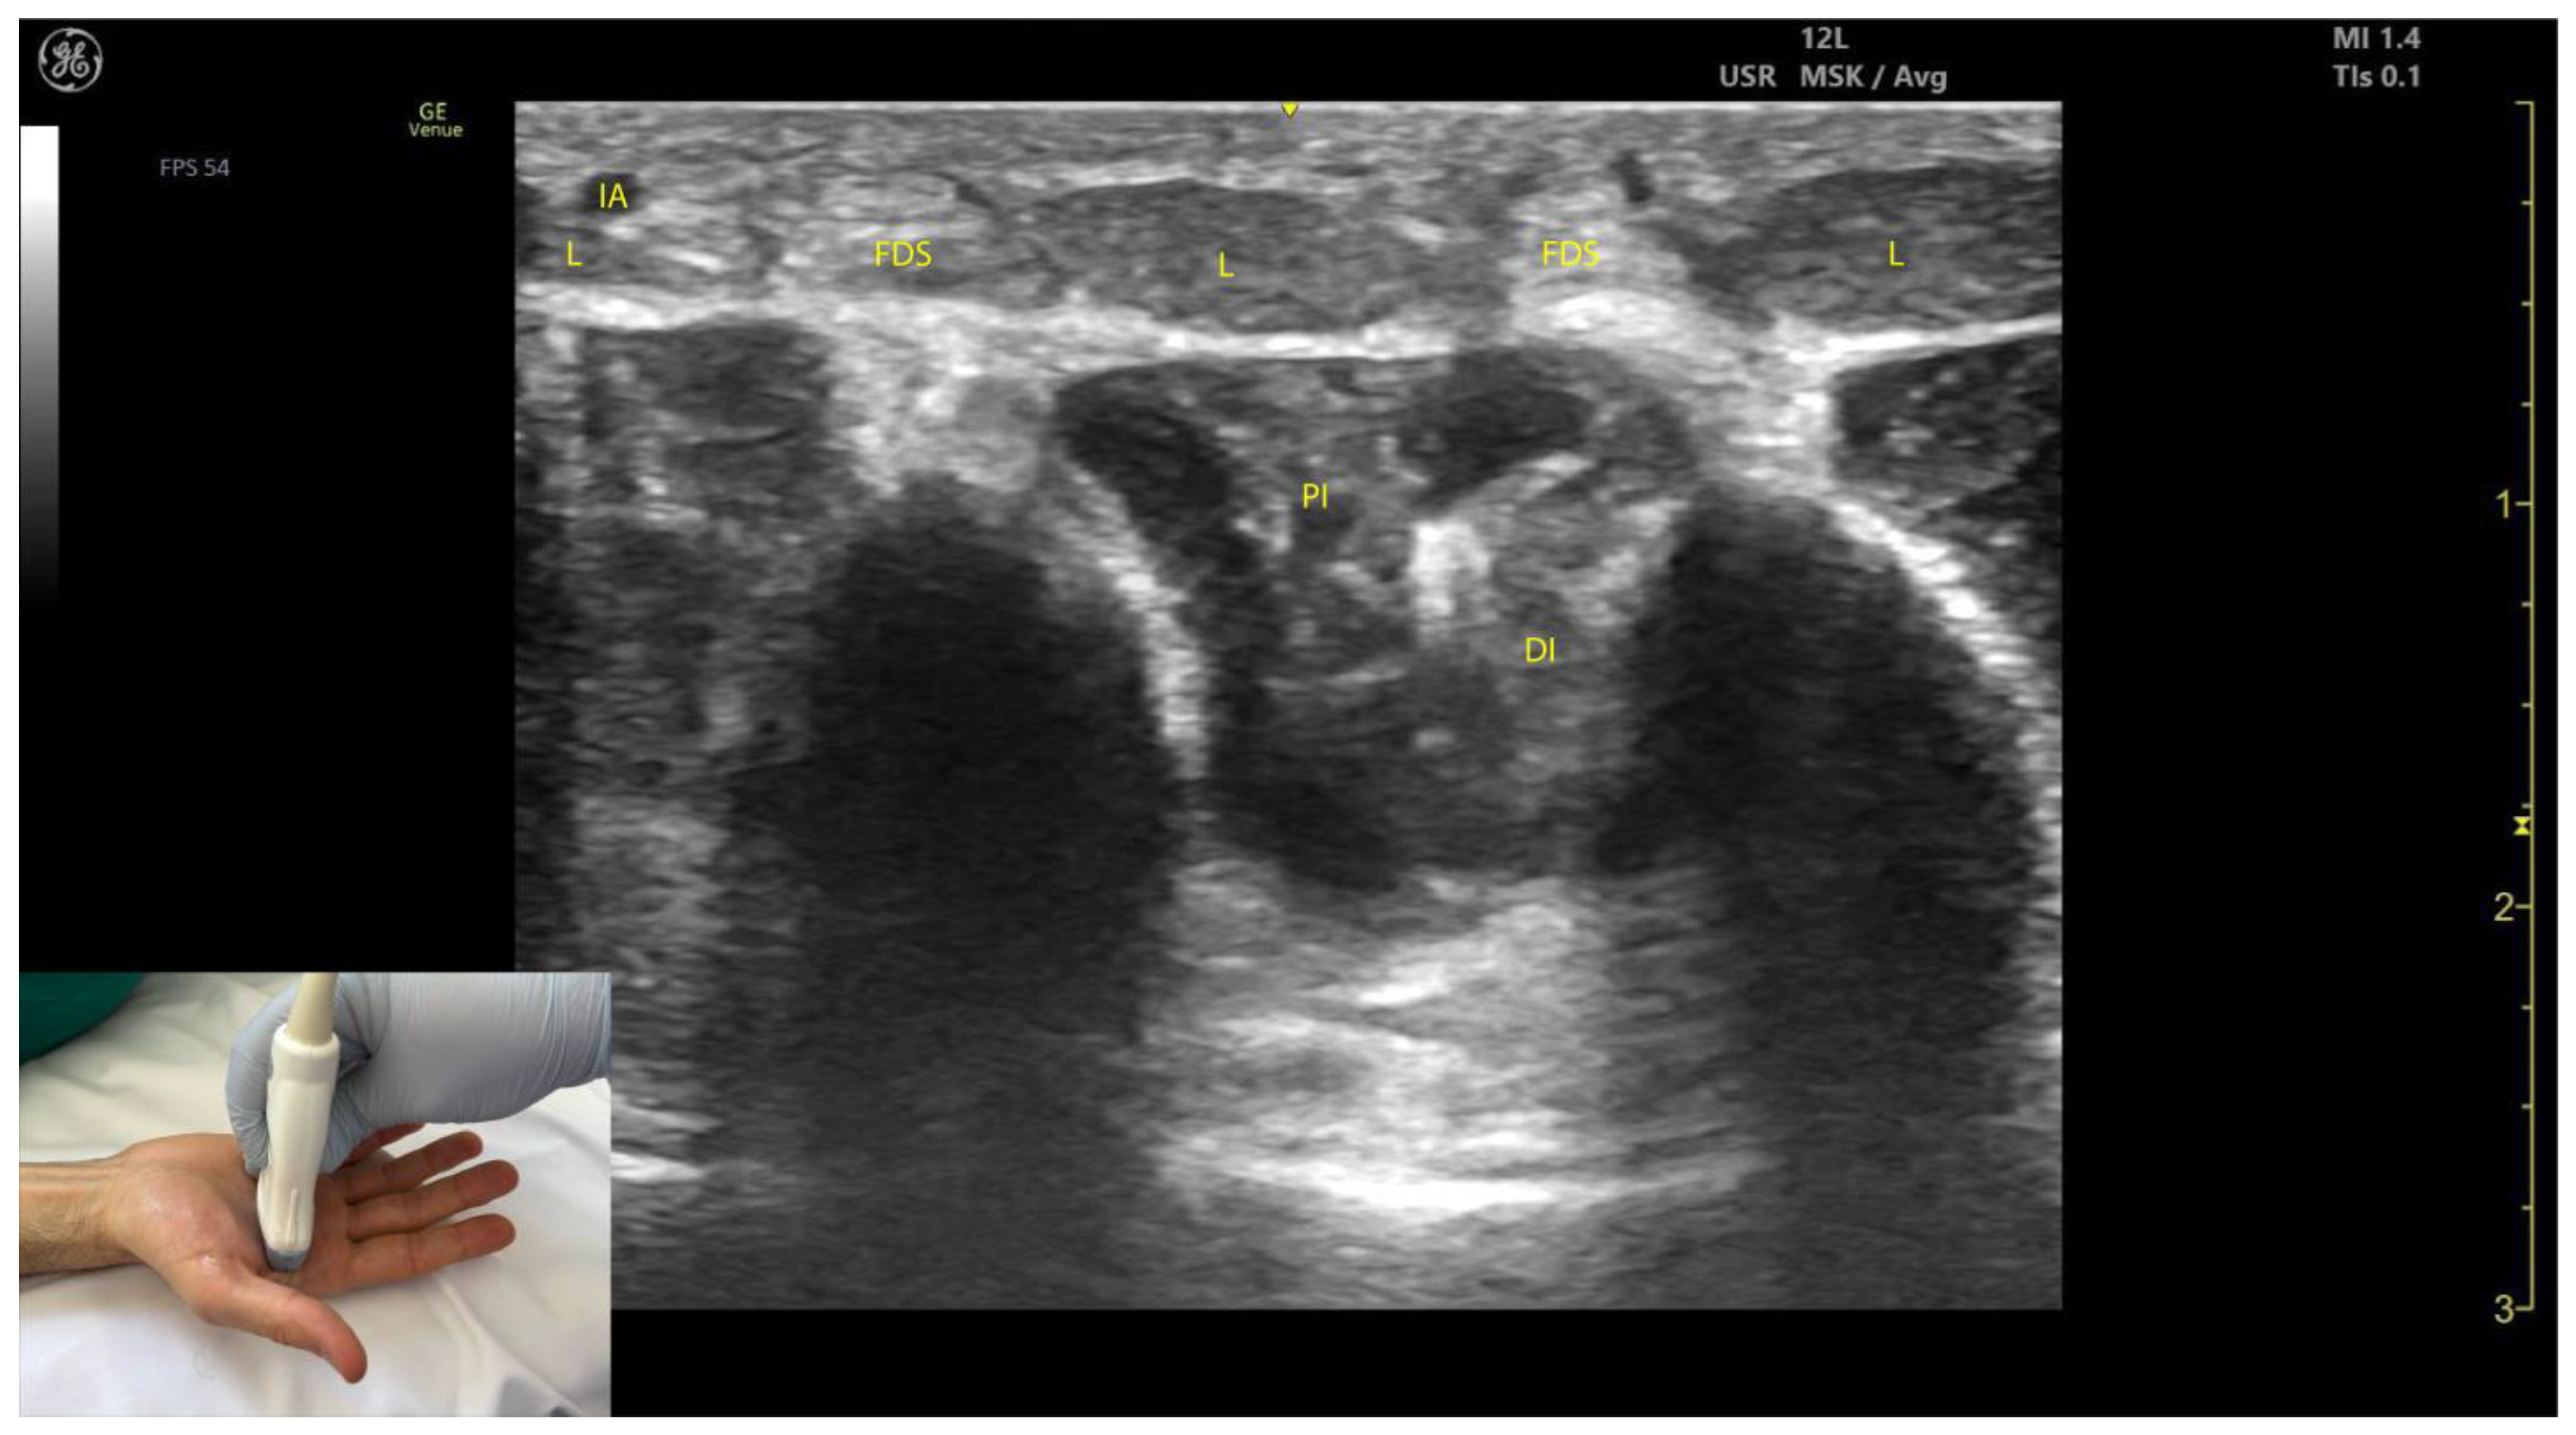

2.12.3. Key Ultrasound Landmarks [63,64,65,66] (Figure 12)

- Muscle morphology: Lumbricals L1 and L2 are unipennate, while L3 and L4 are bipennate. Intramuscular fascia corresponding to L1 and L2 can be visualized.

- Innervation and vascular supply: Superficial to L1 and L2 are branches of the median nerve, while superficial to L3 and L4 are branches of the ulnar nerve, each accompanied by arterial branches from the dorsal carpal arch.

- External fascia: The lumbrical muscles lack a pronounced fascia to distinctly separate them from the FDS tendons (adjacent structures), which may pose challenges for precise localization during BoNT-A injections.

- Dynamic evaluation: Scanning distally toward the MCP joints reveals an increase in the size of L1–L4 and a corresponding decrease in the size of the AP. Placing the transducer at the midpoint of the metacarpals II–V and performing flexion and extension maneuvers of the fingers highlights the contraction of L1–L4 and the associated action on the tendons of FDS and FDP. The lumbricals appear as hypoechoic structures with hyperechoic speckles, described as a “starry sky” pattern, while the FDS and FDP tendons are hyperechoic with parallel fibrillar lines.

2.12.4. Clinical Implications and Injection Strategy

2.13.3. Key Ultrasound Landmarks [60,67,70] (Figure 13)

- Muscle position: The dorsal interossei are the most superficial muscle structures on the dorsal aspect of the hand.

- Muscle morphology: The dorsal interossei are bipennate muscles, whereas the palmar interossei are unipennate. Musculoskeletal ultrasound also allows visualization of the intramuscular fascia within these structures.

- External fascia: The interossei muscles lack a pronounced fascia to clearly demarcate the dorsal and palmar interossei (adjacent muscle masses), which can make precise localization during BoNT-A injections more challenging.

- Muscle size: The first dorsal interosseous muscle is larger compared to the other dorsal interossei. Deep to it lies the AP, which decreases in size as the first dorsal interosseous muscle increases during dynamic scanning cranially.